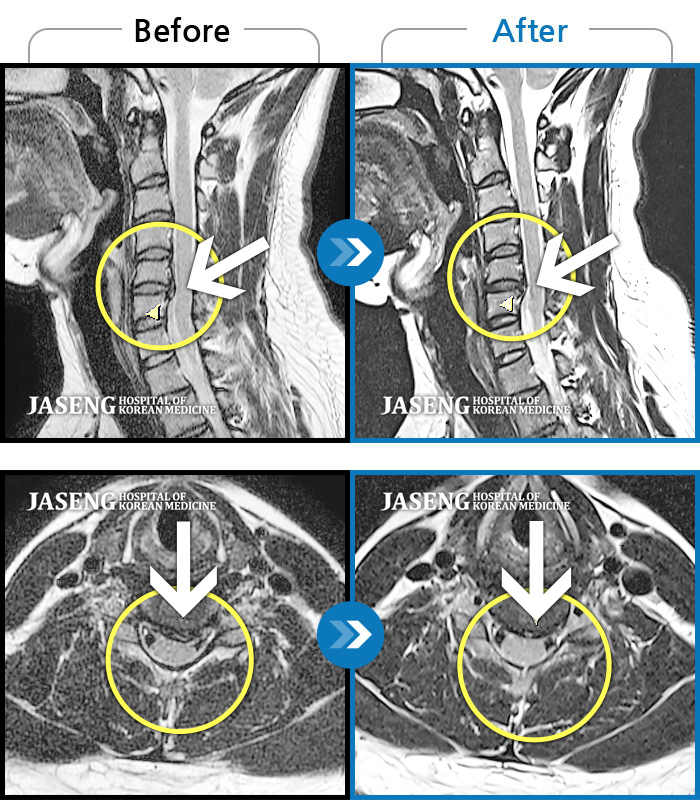

자생 비수술 한방통합치료 후

터진디스크가 흡수된 모습

Before

After

비수술 치료만으로

터진 디스크 흡수

목 통증과 새끼 손가락 저림 및 안정시에도 우측 어깨 통증 호소하여 내원하셨습니다.

2022.08.10 ~ 2024.11.08